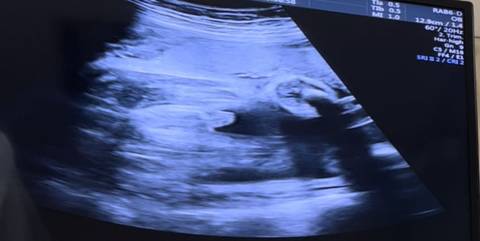

B超单子上宝宝肚子下面一坨圆圆的,看着不像肚脐啊?

医生没有解释吗?脐带的影像吗

图片上面来看,确实不能帮你判断什么,只要检查结果通过的话就证明是没问题的。